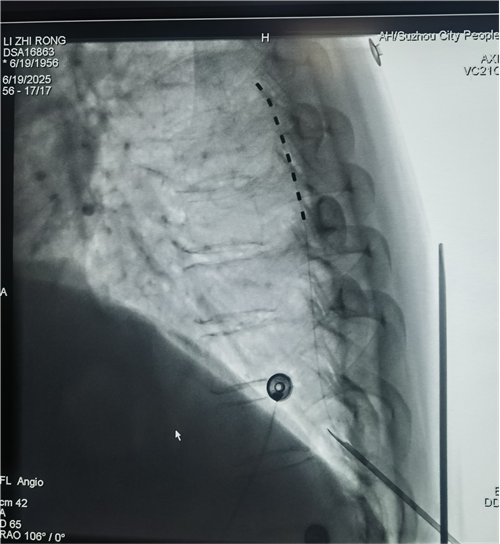

1.微创植入电极:通过微创手术将电极放入椎管硬膜外腔,位置相当于脊髓“信号中转站”;